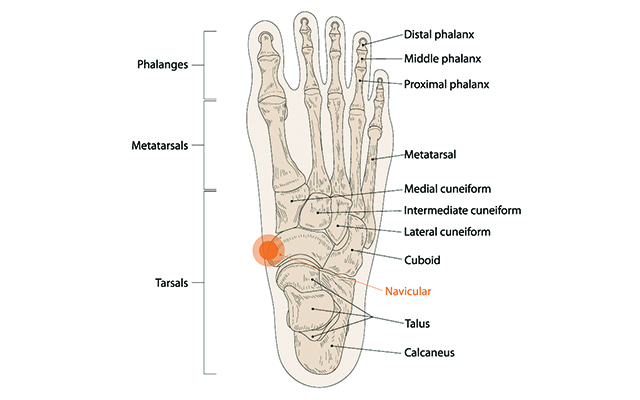

우리 발의 안쪽에는 엄지발가락과 발목을 이어주며

걷거나 뛸 때 충격을 흡수해 주는 주상골이라는 뼈가 있습니다.

우리 발의 안쪽에는 엄지발가락과 발목을 이어주며 걷거나 뛸 때 충격을 흡수해 주는 주상골이라는 뼈가 있습니다.

부주상골은 발목뼈 중 주상골 옆에 위치하는 부골(accessory bone)로서 청소년기에 주상골과 하나의 뼈로 유합되는데, 유합하지 못하고 남아있는 것을 말합니다. 부주상골은 인구의 10~20%에서 발견될 만큼 흔합니다.